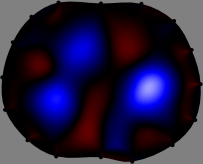

Figs. 3 and 4 compare the performance of the proposed FER method in (20) with the standard regularized least-squares method ((19) when is the identity matrix). The regularization parameter of the standard method was heuristically chosen for its best performance, and the parameter of the FER method was set to be one of three different values . The injection current was 1 mA at 100 kHz, and the frame rate was 9 frames per second. The reference frame at was obtained from the maximum expiration state. The measured data, , represent the voltage differences between each time and . The blue regions, which denote where conductivity decreased by inhaled air, increased during inspiration and decreased during expiration. The FER method with was clearly more robust than the standard method that produced more artifacts originated from the inversion process.

| FER () | |

||||||||||

Note that the degree of orthogonality of the columns of the sensitivity matrix depends on the current injection pattern. This makes the performance of the FER method depend on the current injection pattern since it incorporates the structure of the sensitivity matrix in the regularization process. For example, if we inject currents between diagonal pairs of electrodes, the corresponding sensitivity matrix becomes less orthogonal compared with that using the neighboring current injection protocol, thus producing more blurred images. In contrast, a more narrower injection angle, for example, using a 32-channel EIT system with the adjacent injection pattern, can enhance the orthogonality of the corresponding sensitivity matrix. However, the narrower injection angle results in poor distinguishability[14] and may deteriorate the image quality. To maximize the performance of the FER method, balancing between orthogonality of the sensitivity matrix and distinguishability should be considered when designing a data collection protocol.